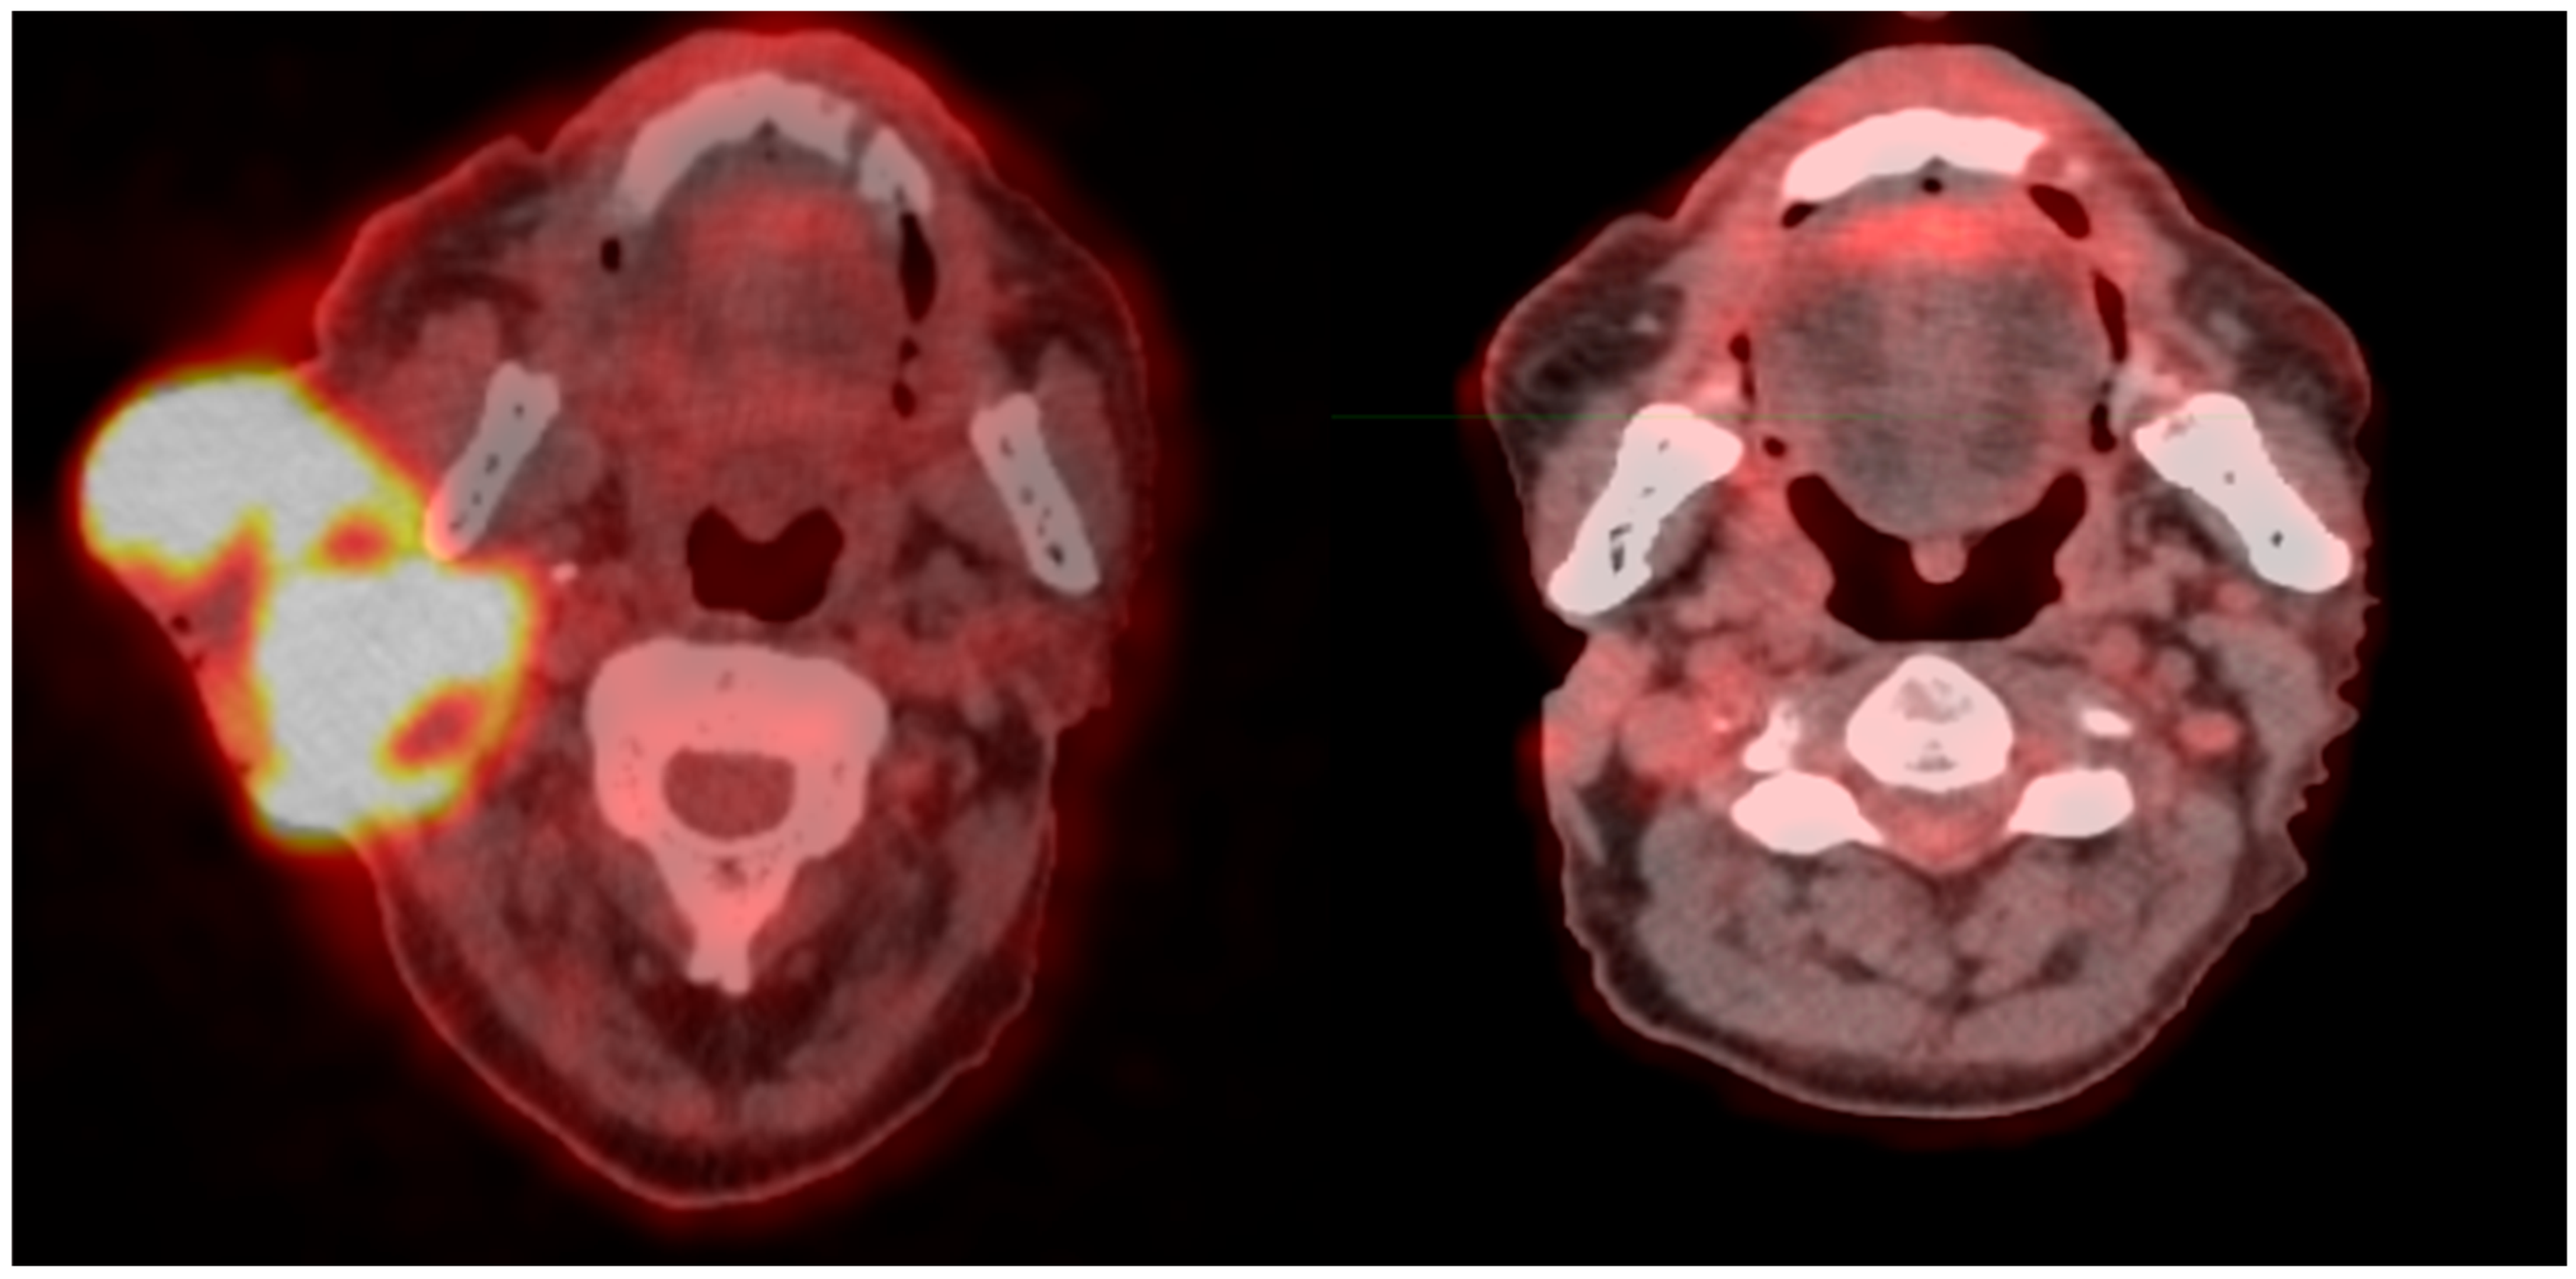

- Ferini, G.; Parisi, S.; Lillo, S.; Viola, A.; Minutoli, F.; Critelli, P.; Valenti, V.; Illari, S.I.; Brogna, A.; Umana, G.E.; et al. Impressive Results after “Metabolism-Guided” Lattice Irradiation in Patients Submitted to Palliative Radiation Therapy: Preliminary Results of LATTICE_01 Multicenter Study. Cancers 2022, 14, 3909. [Google Scholar] [CrossRef] [PubMed] [PubMed Central]